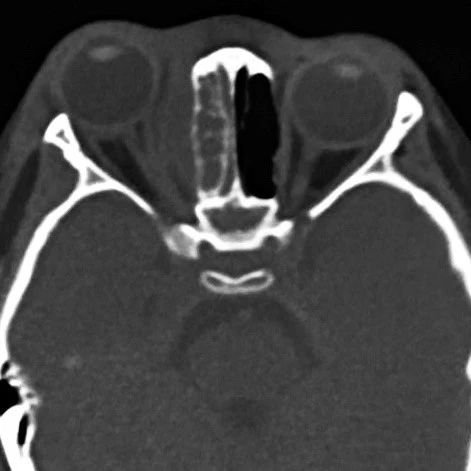

术前(左)与术后(右)对比

手术后,多学科专家团队密切观察患儿病情变化,每日进行查房讨论。术后第1天,患儿的体温和血液感染指标恢复正常,第2天查房时,小姑娘就在病房里睁着水灵的大眼睛和妈妈玩游戏了。